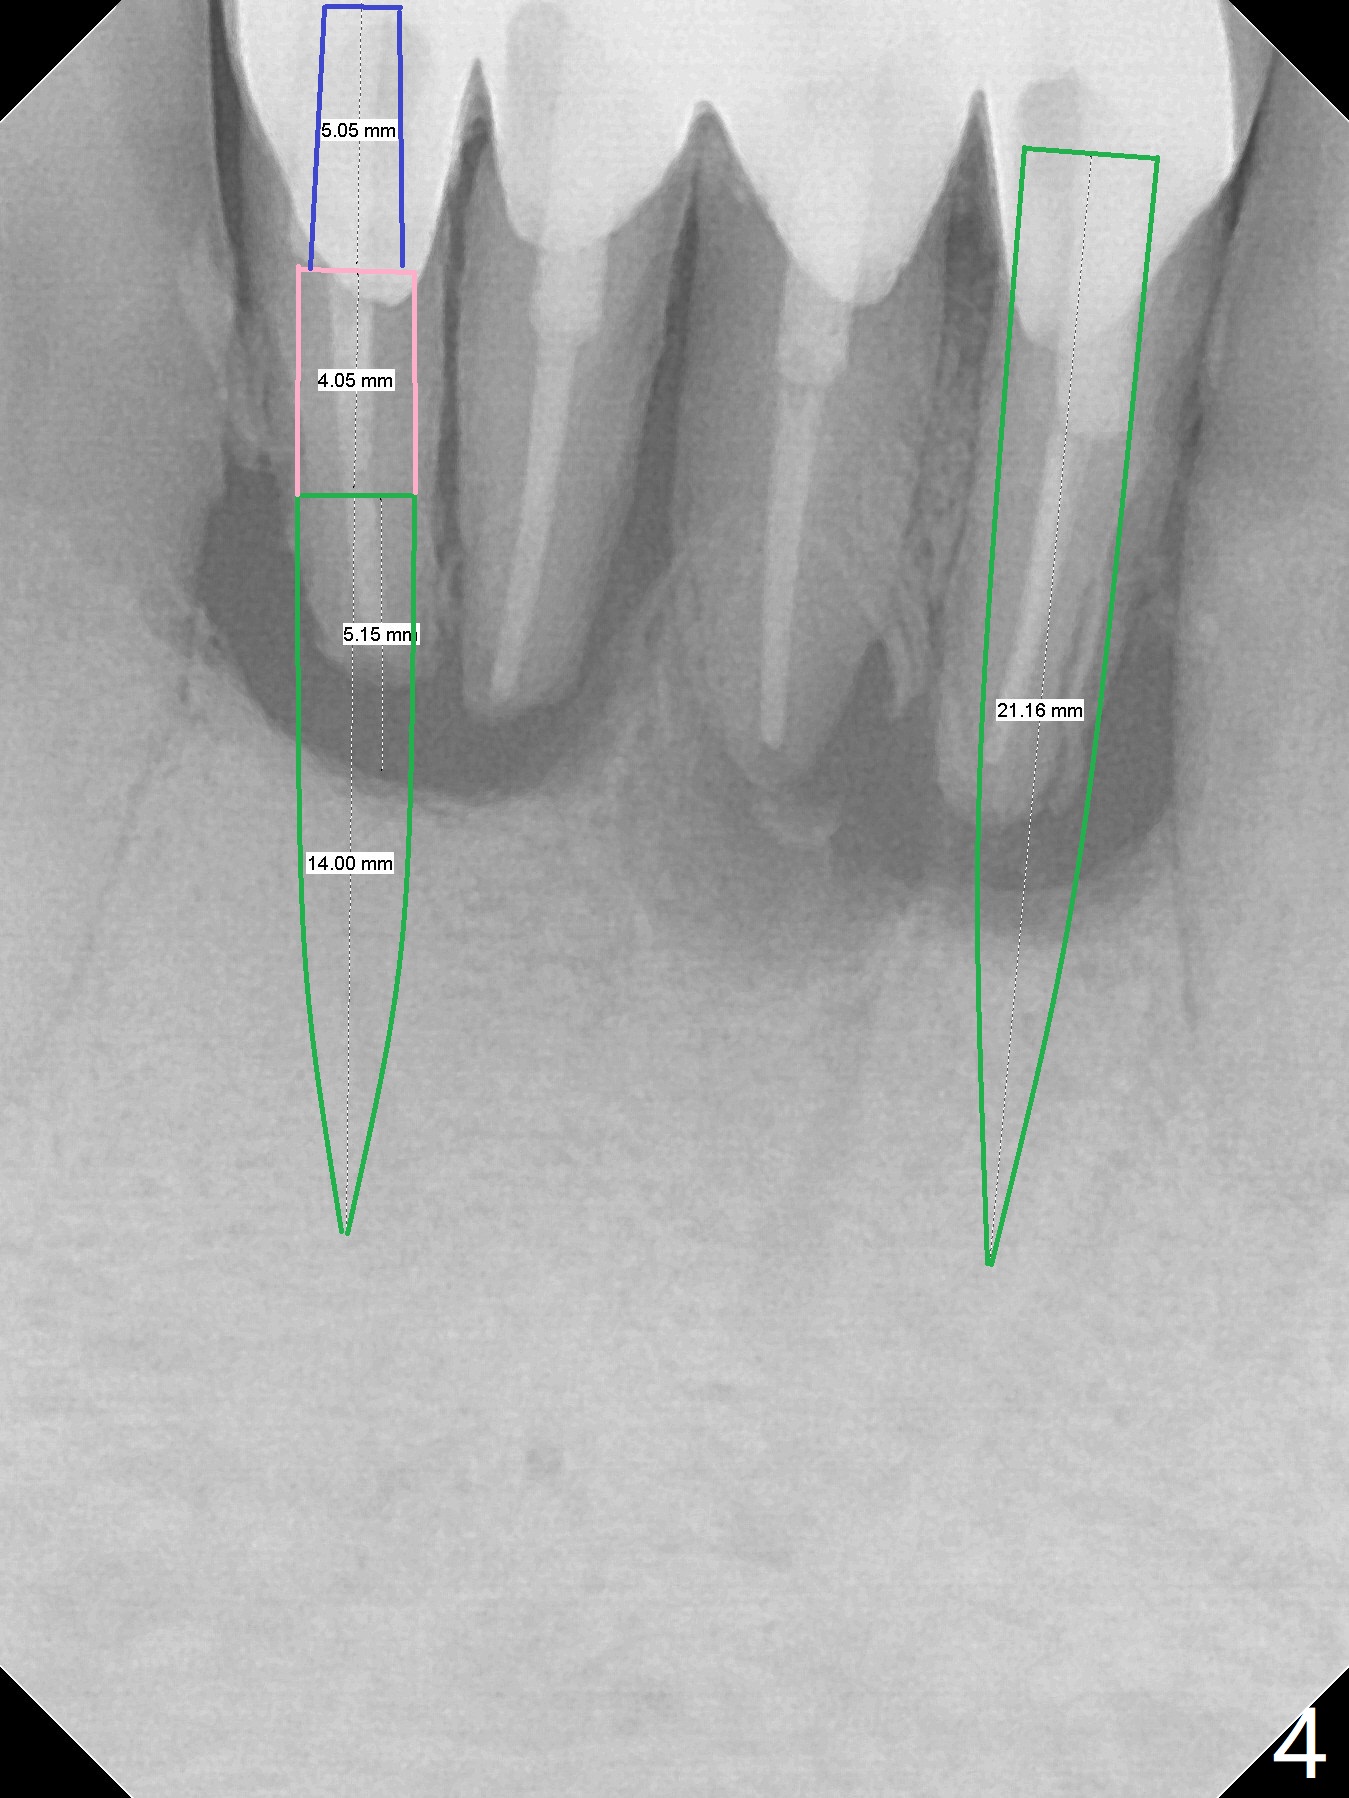

A 58-year-old man with splinted crowns at #23-26 has buccal abscess and lingual gingival recession at #25 and 26 (Fig.1,2). Large periapical radiolucency involves all of the 4 incisors (Fig.3). Note residual crestal bone between the incisors (*). It appears that a 1-piece implant with 4 mm cuff (Fig.4 pink) should be placed on the right side, while a longer 1-piece implant (23 mm) with shorter cuff (1.5 mm) on the left side. A provisional FPD will be fabricated from a stent.